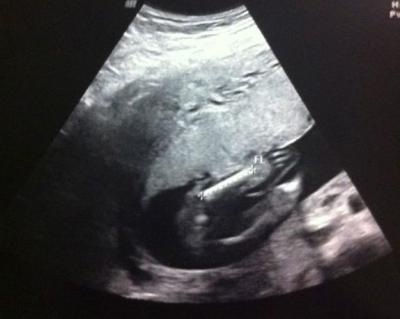

Typisch ich halt... Wollte aus der Wanne raus und PLUPS hats mich dermaßen hingehauen, das ich erst mal nicht mehr wusste wo oben und unten ist... Gleich meinen Hausarzt angerufen, der meinte sofort ins krankenhaus... Dort fix und fertig angekommen, ENTWARNUNG... Baby gehts gut, GOTTSEIDANK! Die Ärztin, die Dienst hatte war suuuper nett (nett ist noch untertrieben) so eine liebe und symphatische Frau, denke noch keine 30! Hat sich ewig viel zeit genommen und bestimmt ne viertel stunde geschallt... Mäuschen ist 16 cm groß und wiegt 200 gramm UND wir bekommen wieder ein MÄDCHEN Sie sagte, also sie hat jetzt drei mal geschaut und ist sich ziemlich sicher, Madame´ist sehr aktiv und hat sich von ihrer besten seite gezeigt... Ich bin so erleichtert das alles oke ist! Wollte "nur" kurz bericht erstatten, ICH FREU MICH SO Anbei der Beweis... :) Achja, und sie meinte das ich ein ziemlich schmales becken habe, 3500 gramm wären noch ok, aber mehr würde dann anstrengend werden, mal gucken, meine große hatte damals 3190 Ich wünsch euch ne Gute Nacht!

Bild zu Krankenhaus... - Forum für August - Mamis

Ist "sie" das???